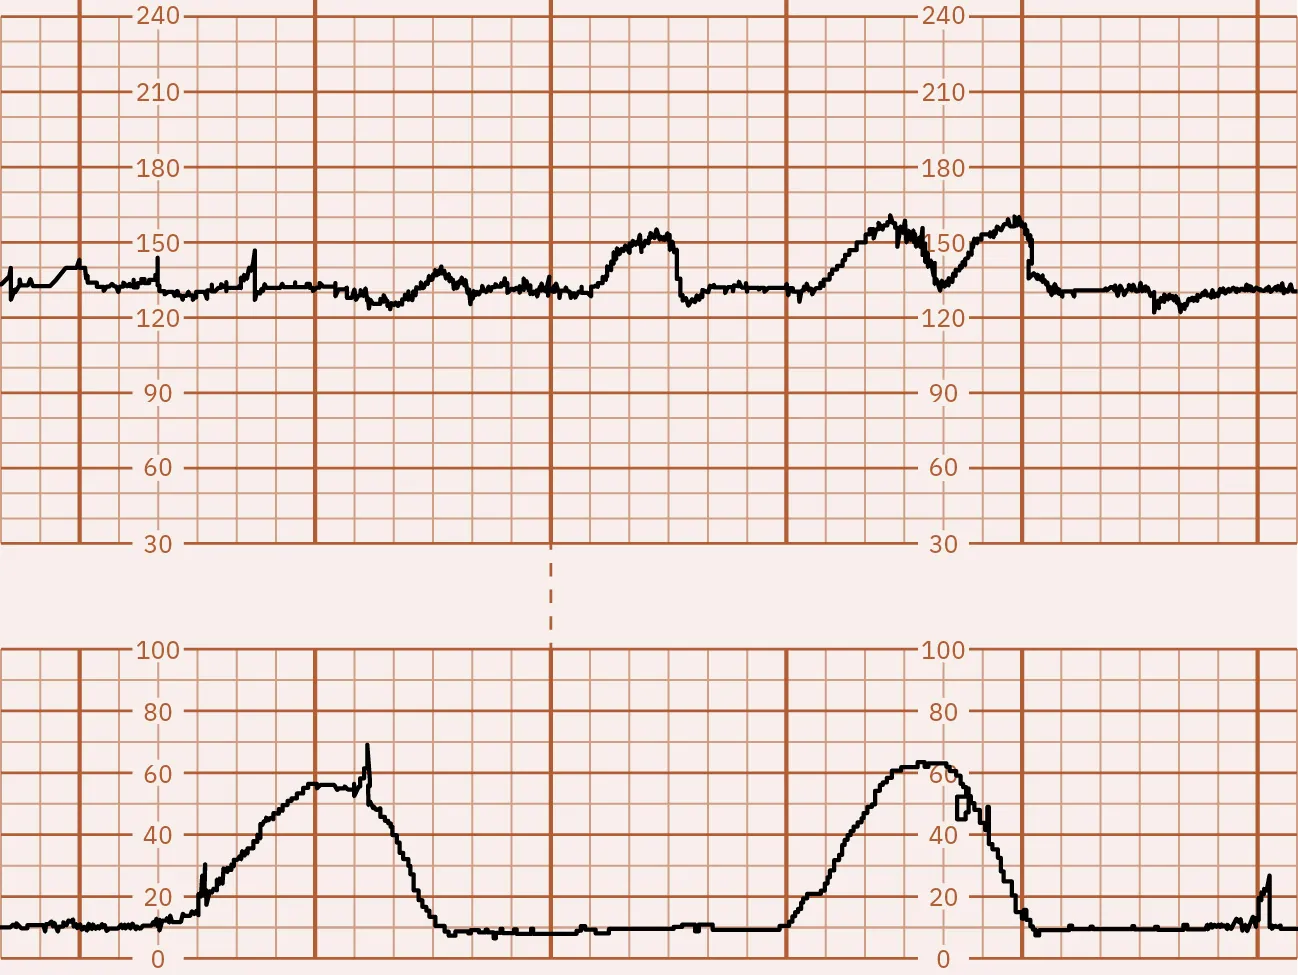

The CST test results are divided into several categories:

• Positive: Late decelerations occur after 50 percent or more of contractions, even if the contraction frequency is less than three in 10 minutes (Figure 13.12).

Fetal monitor tracing graphic depicting positive CST. Top strip displays dips in lines after second strip shows spikes.

Figure 13.12 Positive CST In this illustration, the FHR baseline is 130. The fetal heart rate is at the top and the contractions are on the bottom. This strip shows a dip in the fetal heart rate just after a contraction occurs, known as a late deceleration. (attribution: Copyright Rice University, OpenStax, under CC BY 4.0 license)

Fetal surveillance with a CST is done to identify the fetusโ€™s risk of hypoxic injury or death so that appropriate intervention can be done to prevent an adverse outcome if possible. It can also identify normally oxygenated fetuses to allow pregnancy to continue safely and avoid unnecessary intervention (ACOG, 2021d).

The nurse can help prepare the pregnant person for a CST by explaining why the test is recommended, answering any questions, and describing what will happen during the test. Prior to the CST, the nurse will need to get a baseline tracing, and the nurse will monitor the tracing afterwards while a plan of care is being determined. The provider will review the results directly after the test is completed and discuss with the pregnant person if continuing the pregnancy, further testing, or delivery is the best plan.